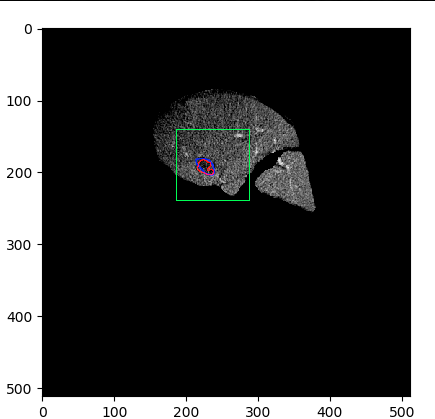

Each pixel of the image is assigned to one of the two classes liver/other tissue and tumor/other tissue, respectively, with a certain probability. Results of the automated liver and tumor segmentation are visualized in Figure 3.2. Comparison with ground truth and segmented liver and tumor give rise to the assumption that our approach is highly promising for obtaining high performance metrics. To qualitatively evaluate performance, we applied some of the commonly used evaluation metrics in semantic image segmentation. Performance metrics are summarized in Table 1.

The following approach is to implement a model using two U-Nets , , one on top of the other. The combined network architecture is shown in Figure 1.1. The inputs for both CNNs are grey-scale images of size and their outputs are binary images of size . While the input of the first U-Net is of the form displayed in Figure 3.1, the input of the second U-Net is produced by the output of the first one as explained in Section 2.3.